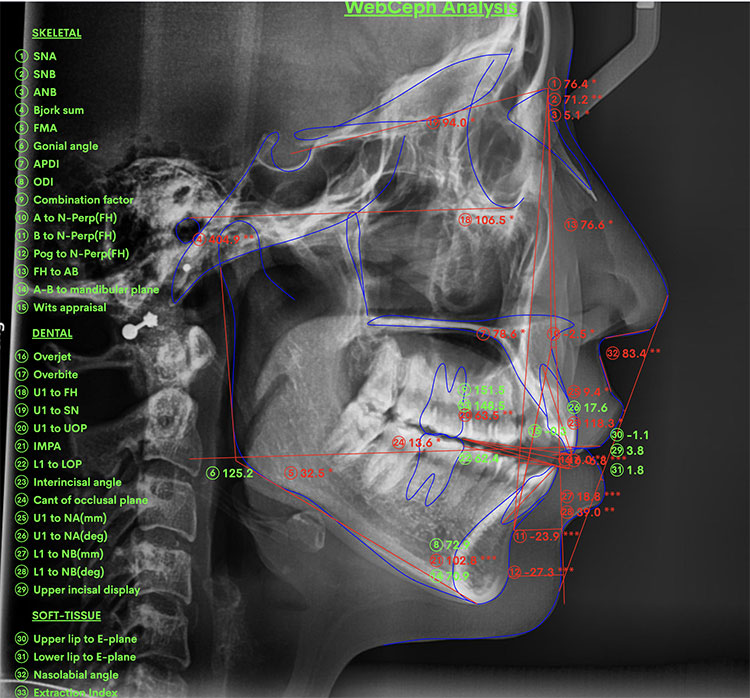

X Quang

Trước |

Sau